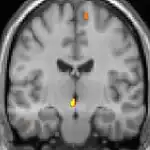

| Positron emission tomography (PET) shows brain areas being activated during pain | ||

Positron emission tomography (PET) scans indicate the brain areas which are activated during attack only, compared to pain free periods. These pictures show brain areas that are active during pain in yellow/orange color (called "pain matrix"). The area in the center (in all three views) is specifically activated during CH only. The bottom row voxel-based morphometry (VBM) shows structural brain differences between individuals with and without CH; only a portion of the hypothalamus is different.[33]